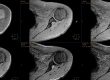

Nell’immagine possiamo notare come nelle immagini superiori che hanno strati più sottili, si possono visualizzare piccole alterazioni a livello dei corpi vertebrali che nelle immagini sottostanti più spesse non sono più visibili.